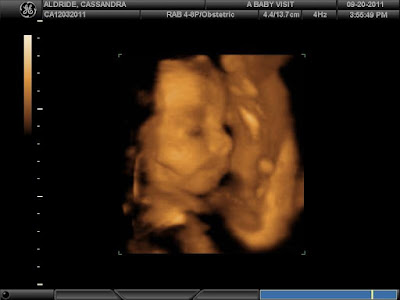

September 20, 2011: Jake and I drove out to Riverside for our 3D ultrasound. We were almost sent home with a return appointment, since Jayden did not want to co-operate! He had his feet up over his head and his hands in front of his face. Eventually, the tech was able to wake him up and we got to see our sleepy boy! :) This was a happy distraction from the devastating news we had just gotten.